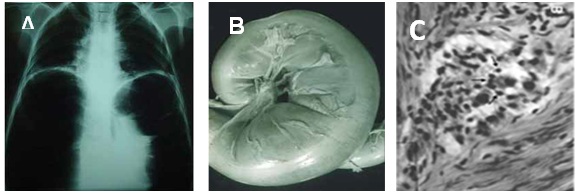

Acute Chagas disease with fever and malaise usually subsides on average of three months. The chronic infection can continue for life without clinical manifestation. However, the pathology manifests in one-third of those with Chagas heart disease (Figure 1), mega colon and mega esophagus (Figure 2).10 The acute infection is diagnosed by parasitological demonstration and by specific IgM antibody 15 days after parasite acquisition10. The chronic T. cruzi infection specific IgG antibody is showed by indirect immunofluorescence (IIF) and enzyme-linked immunosorbent assay (ELISA). The health facilities rely on trade mark kits of these assays to disclaim blood donors, and an automated chemiluminescent kit showing 97.6% specificity can be used for the diagnosis of Chagas disease in health facilities.8

Figure 1 The heart pathology in Chagas disease. A) Cardiomegaly shown by chest X-Rays. B) Rejection and lysis of parasite-free heart cells (circle) by autoimmune lymphocytes. C) Rejection of parasympathetic neurons (arrows) by lymphocytes. Photographs from doctor Teixeira’s file.